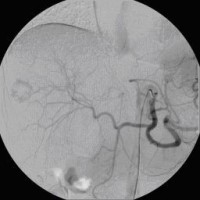

Superselektive transarterielle Chemoembolisation (TACE) mit Sondierung eines tumorversorgenden Gefäßes 2

(Bild 4 von 5)